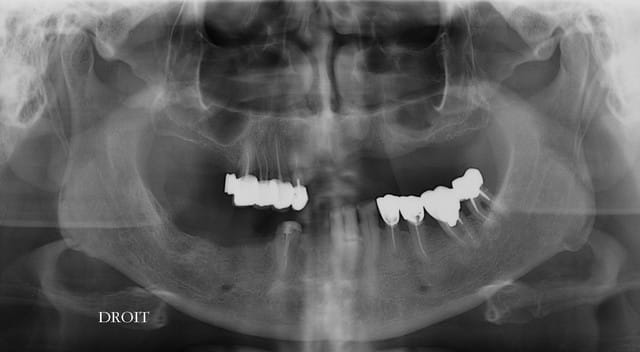

sur le pano : pas de problème particulier (même si la crête semble fine) mais pas assez de données.

Merci pxav,en réalité c'est une patiente d'une collégue qui demande un avis, et c'est l'image de l'os au niveau 22 ,23 qui m'inquiéte,

c'est l'image de l'os au niveau 22 ,23 qui m'inquiéte,

qu'est ce qui te gène?le manque de hauteur?

c'est vrai que l'on a une impression de tissus osseux "flottant" au dessus de la crête.

Y a t-il eu déjà une greffe ? un comblement type xenogreffe ? une racine comme sous le cantilever en bas....

y'a t il un scan ou au moins des rétro alvéolaire pour préciser ?

sinon, le cas ne parait pas dramatique, un peu comme ça:

T'as pas dû regarder la mandibule mon gars. C'est elle le vrai blème...